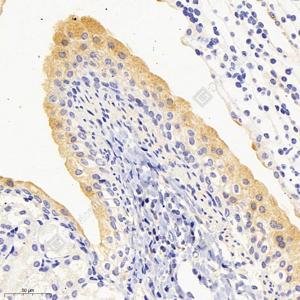

IHC检测NAT1蛋白(货号 GB113653). 样品: 小鼠膀胱, 4%多聚甲醛 (货号G1101) 固定12-24小时. 抗原修复: 柠檬酸抗原修复液(干粉, pH 6.0) (G1201), 98℃, 20分钟. —抗: 1: 2000稀释, 4℃ 孵育过夜. 二抗: HRP标记山羊抗兔IgG (H+L) (货号GB23303), 1: 200稀释, 室温孵育1小时. |

IHC检测NAT1蛋白(货号 GB113653). 样品: 大鼠膀胱, 4%多聚甲醛 (货号G1101) 固定12-24小时. 抗原修复: 柠檬酸抗原修复液(干粉, pH 6.0) (G1201), 98℃, 20分钟. —抗: 1: 1600稀释, 4℃ 孵育过夜. 二抗: HRP标记山羊抗兔IgG (H+L) (货号GB23303), 1: 200稀释, 室温孵育1小时. |